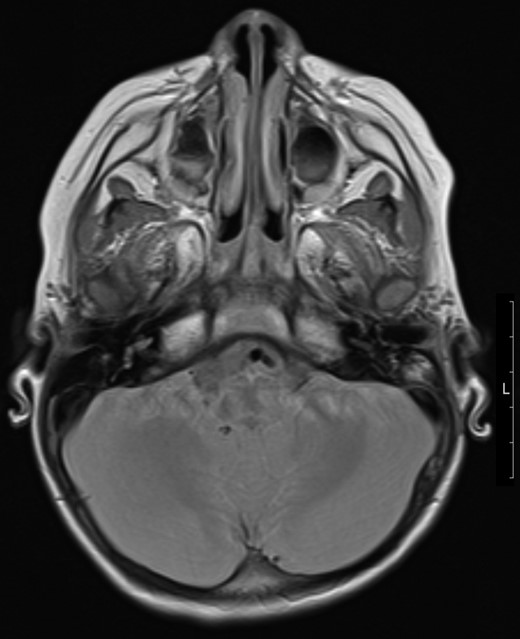

Patient underwent MRI imaging (Day 6 post drainage) which showed near resolution of the epidural and extracranial collection (Fig. 3). Upon review of images it was decided that no further surgical input was necessary, and the patient was discharged with follow up planned within 2 weeks.

Transverse magnetic resonance image 3 months post op showing some residual inflammation within the post-surgical mastoid cavity (white asterisk) and resolution of collection.